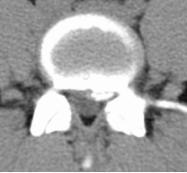

70岁的梁奶奶,家人说老人家因提重物导致腰背疼痛,正因疫情期间,在家休息仍无缓解,因疼痛无法正常生活,迫于为梁奶奶解除痛苦,居家7天后家人带其来到我院就诊,张昊主任医师阅读了相关影像学资料,经过团队的讨论,首先明确诊断为 “1.胸12、腰1椎体压缩性骨折 2.重度骨质疏松症”。针对老年人骨质疏松导致椎体压缩性骨折的治疗,把相关治疗方案以及相应的风险等事宜详细告知家属,最终采用经皮穿刺椎体后凸成形术为梁奶奶进行手术,术后疼痛明显缓解,效果非常满意,第二天顺利出院。

术前影像